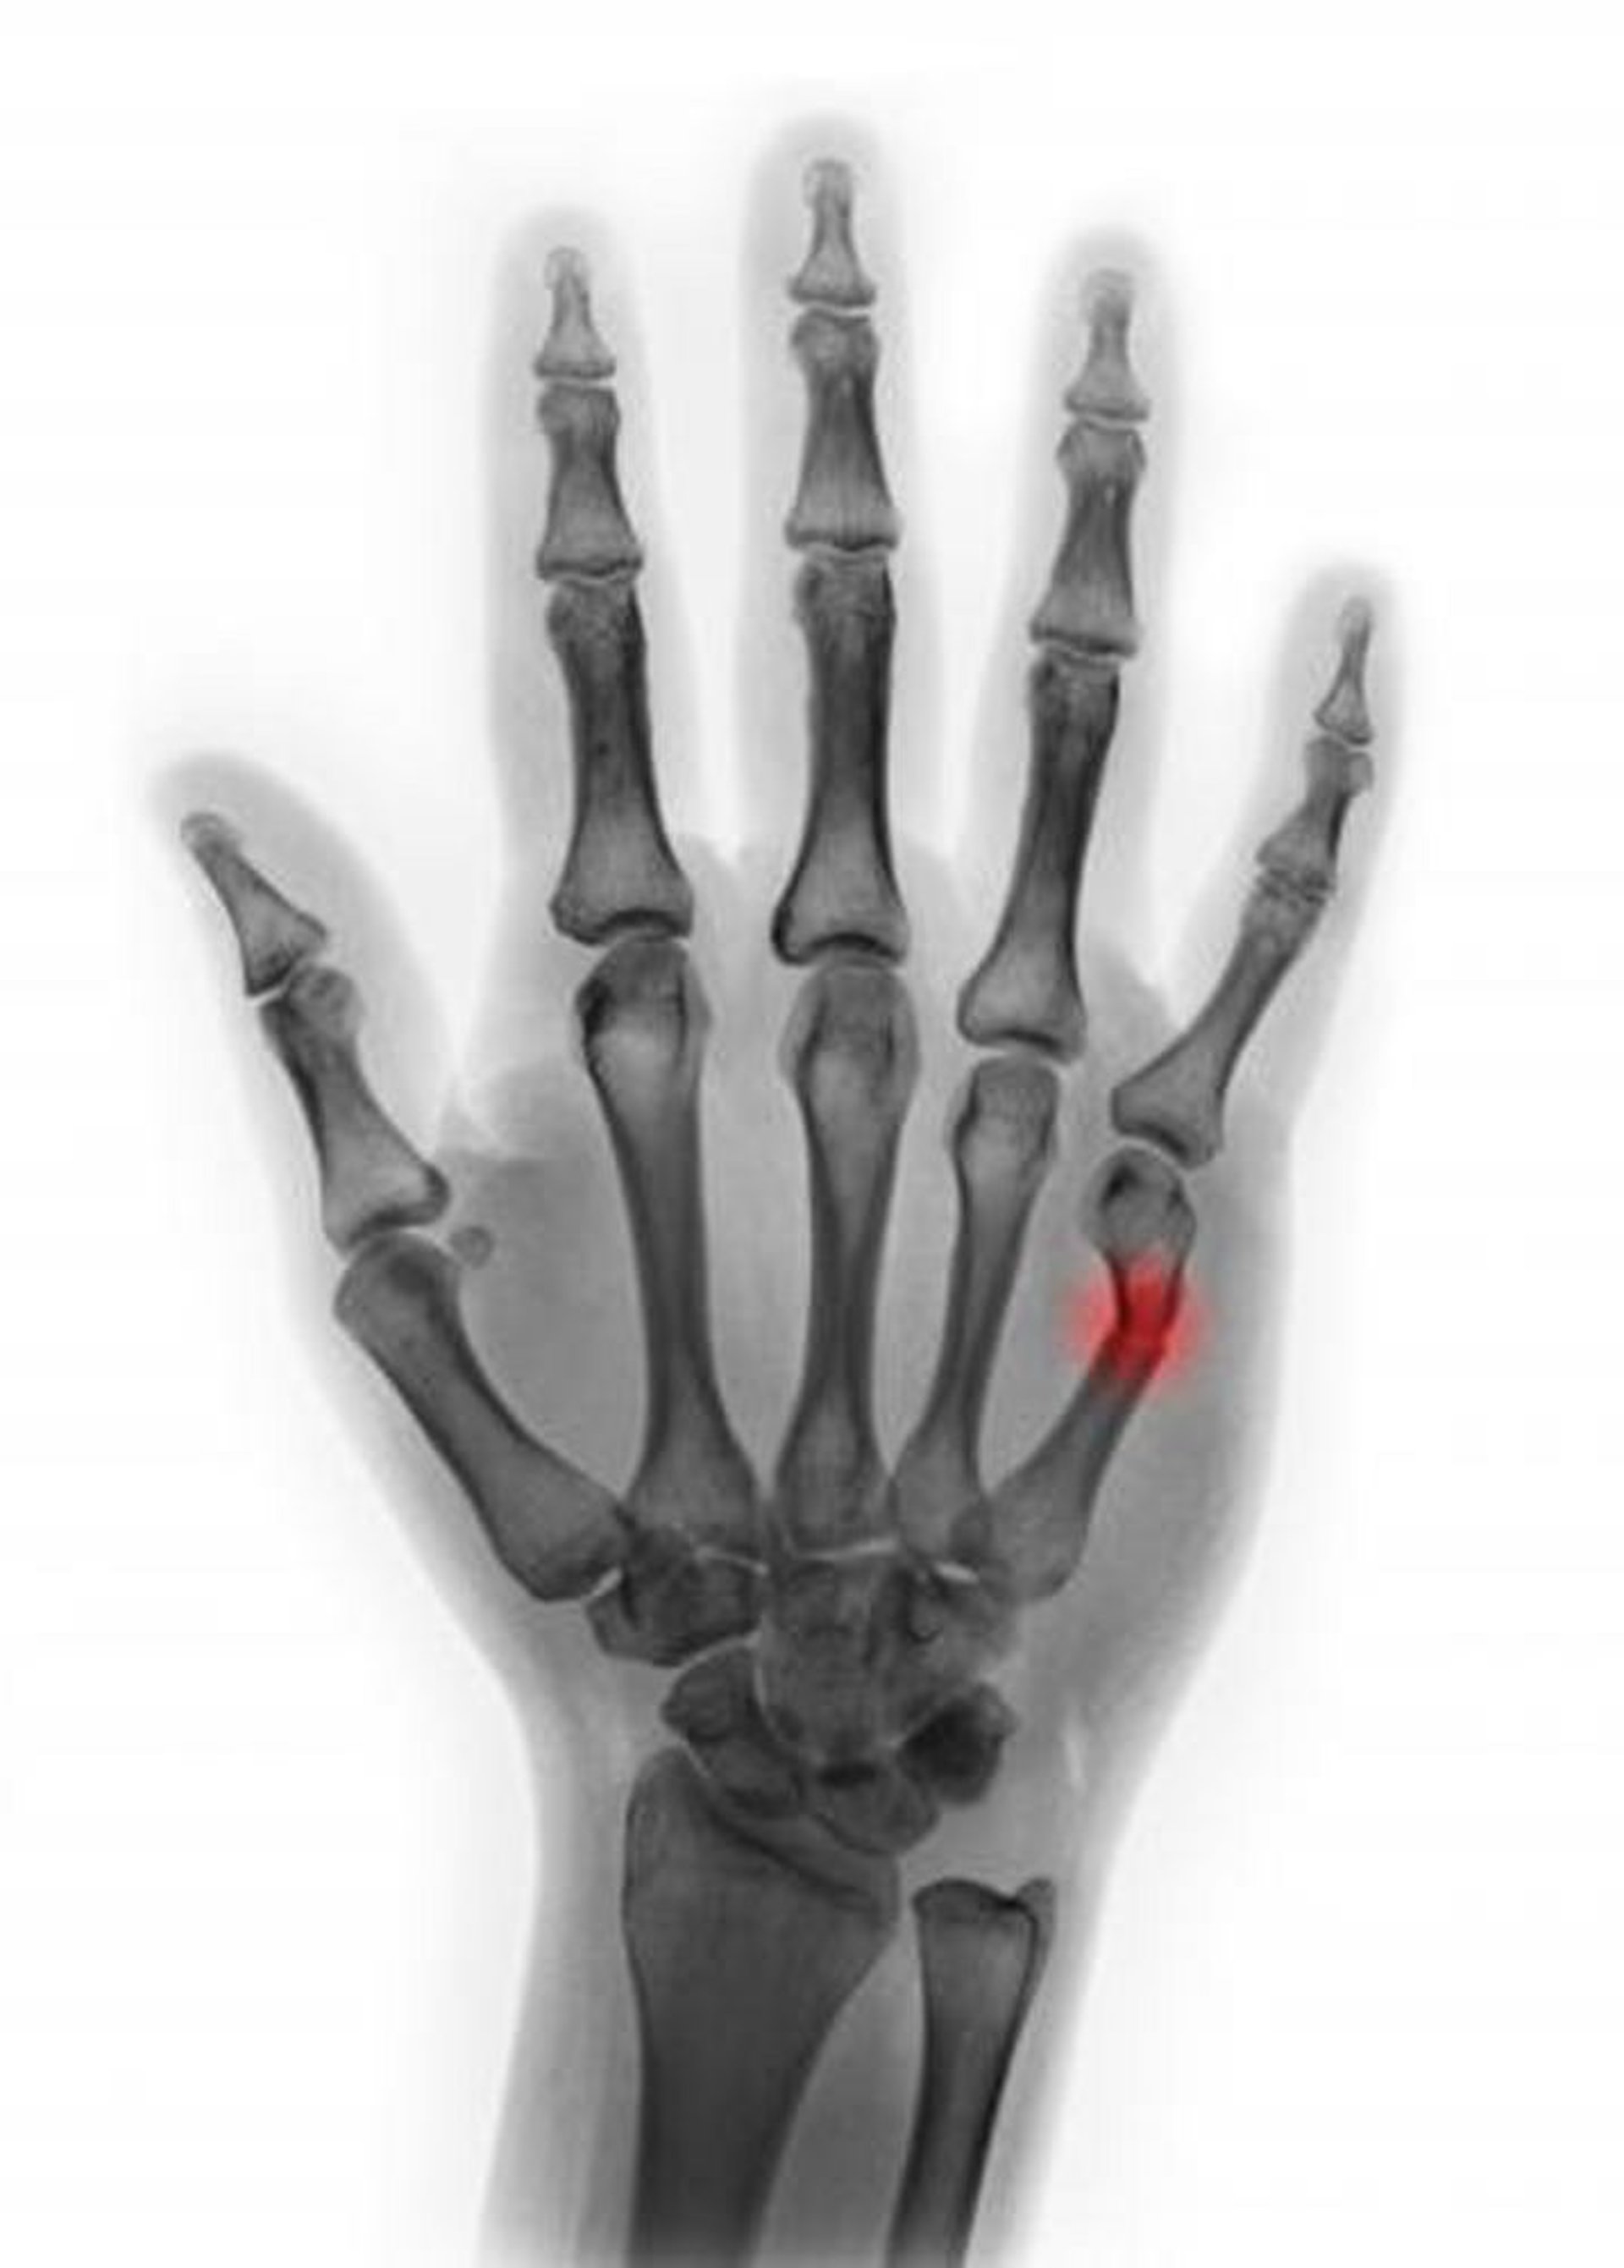

Fraktur des 5. Mittelhandknochenhalses

Diese farbige Röntgenaufnahme zeigt eine Fraktur des 5. Mittelhandknochens. In dieser Ansicht scheint die Angulation < 45° zu sein, was darauf hindeutet, dass eine Reposition nicht erforderlich ist.